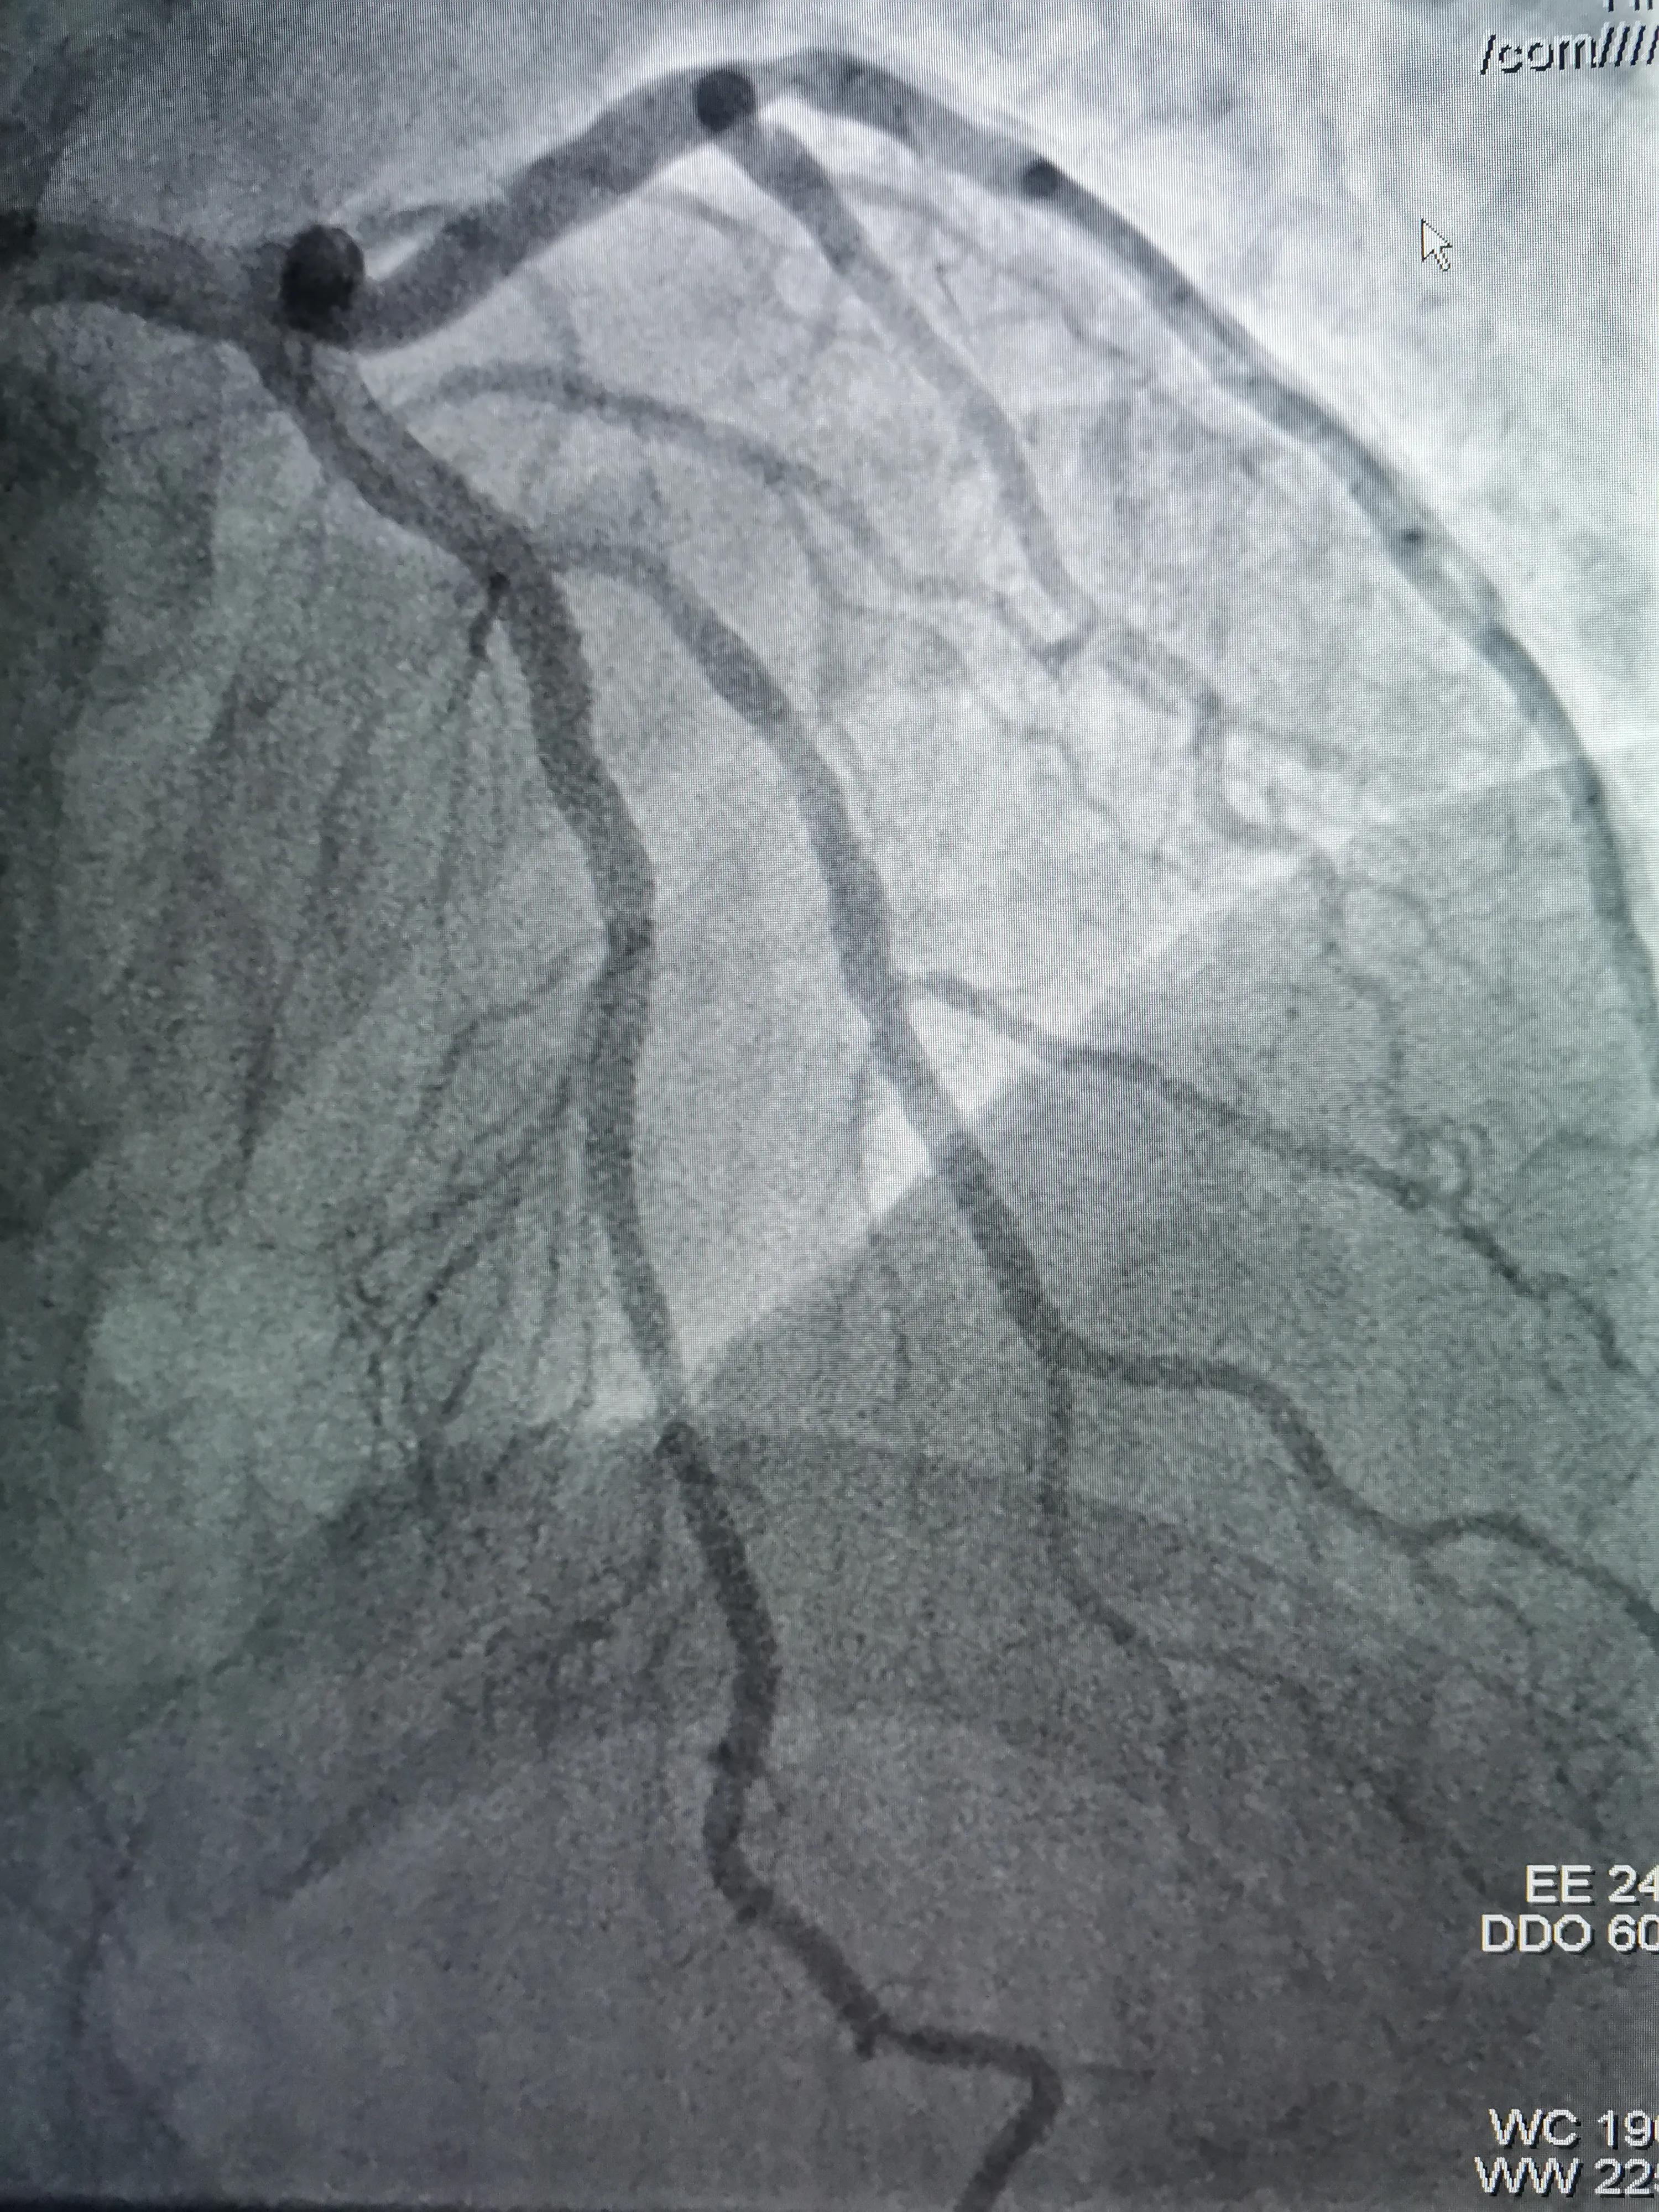

复查造影,支架完全贴到血管壁,分支开口受累狭窄消失,影像效果满意决定分支不再植入支架,结束手术。